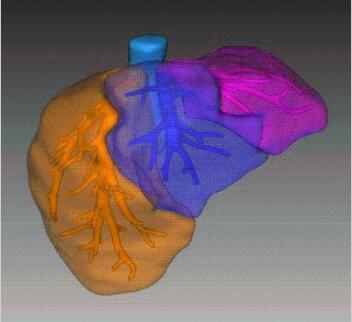

Segmentation

Segmentation of tissue (e.g., isolating the brain, differentiating gray and white matter) is performed using region-growing methods, filter operations as well as the application of 3D templates. Using the mouse it is very easy to explore a 3D volume with superimposed pseudocolor-coded statistical maps in a four-window representation showing a sagittal, coronal, transversal and oblique section. Based on a (segmented) 3D data set a three-dimensional reconstruction of the subjects' head and brain can be calculated and displayed from any specified viewpoint using volume or surface rendering.

Advanced segmentation tool means even higher quality segmentation of grey and white matter and boundaries.

Volume Rendering

Volume rendering is performed with a very fast ray casting algorithm; lightning calculations are based on Phong-shading. Surface rendering of reconstructed surfaces is performed using OpenGL. Using texture mapping, a reconstructed surface (e.g., head or brain) may be sliced in real time, showing both surface and volume data at the same time. Initial polygon meshes serve as the basis for surface finding, cortex inflation and cortex flattening computations.

Surface Reconstruction

The surface reconstruction procedure starts with a sphere (recursively tesselated icosahedron) or a rectangle, which slowly wraps around a (segmented) volume data set. In order to avoid topological defects and to let the surface smoothly grow into deep sulci, a dynamic mesh algorithm was developed which automatically invents new polygons on the fly at places where they are needed. A reconstructed cortical surface may be inflated, cut interactively and slowly unfolded minimizing areal distortions. Statistical 3D maps may be superimposed on reconstructed, inflated or flattened cortex. Signal time courses may be invoked by simply pointing to any region of a visualized surface.